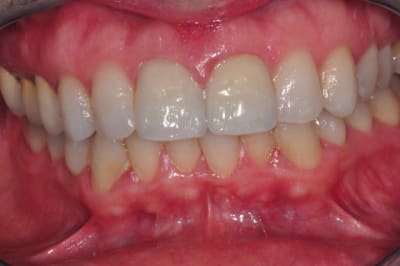

Je dirais défaut de cuisson, ça t'explique que les trois couronne sois touché de maniéré homogène, mauvaise porosité qui est passé inaperçus a la pause. Avec les habitues de ton patient (fumeur?), les défauts se remplisse de colorant noir et deviennent évident. Ta pas une grosse fêlure moche sur le milieux de la face vestibulaire de chaque dents?

A priori je dirais trop de cuisson.

Mauvaise gestion de l'état de surface au labo avant la cristallisation, et voir quel programme de cuisson a été appliqué court ou long.

Moins c'est cuit moins c'est cristallisé

Si l'état de surface est pollué avant glaçage et cuisson on a ce genre de défauts.

si les retouches en phase bleu de métasillicate sont faites avec les mauvaises fraise ou pointe montées....si...

Si la glasure est mal passée.....

16/10/2012 à 20h09

ça sent la cuisson sans vide ça .....

non, sortie du four, une ceram n'a pas cet aspect , il n'y a pas de bulles comme ça, soit c'est une infiltration car il a cuit sur du réfractaire et donc l'air est passé au travers ...

sur les Emax, nous nous sommes rendus compte que pour éviter les porosité, il fallait passer la surface à la meule caoutchouc,.

moi je dirais une cuisson glaçage , rajout de céramique de correction avec recouvrement de glasure .. tout en un ..

et paf bubulle ..

mais je suis d'accord pour dire que ce genre de défaut existent aussi en profondeur (le coté blanc laiteux du rendu) , un polissage n'aurait pas amélioré la situation.

je ne pense pas que cet état de surface soit dû à un manque de polissage, que l'emax soit pressé ou usiné ... là il y a des trous qui se remplissent de merde ...

et puis ce ne sont pas des monoblocs non ? c'est donc la partie stratifiée qui déconne .

je penche comme molinarius pour une correction des formes au glaçage mais avec des poudres à la temp de fusion trop élevée pour un glaçage, les "grains" ne ce sont pas suffisamment aggloméré .